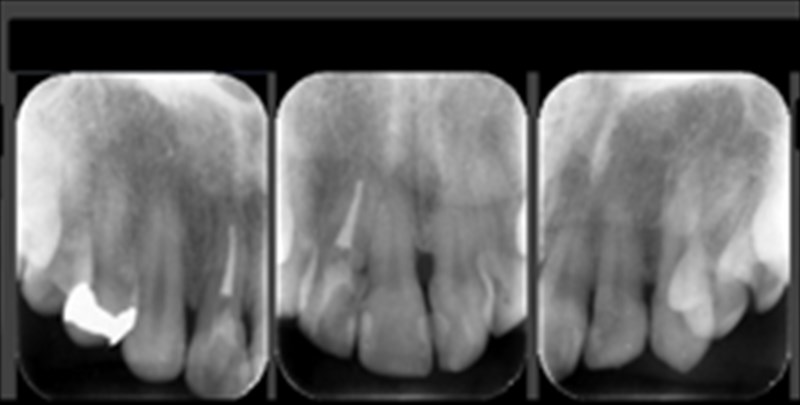

術前のレントゲン

水平的に骨がなくなっていました。